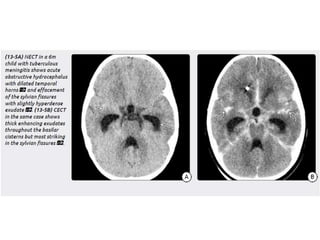

Tuberculous meningitis

• Tuberculous meningitis is the most common presentation

of intracranial tuberculosis, and usually refers to infection of

the leptomeninges.

• Tuberculous meningitis, although seen in all age groups, has a

peak incidence in childhood (particularly 0-4 years of age) in

high prevalence areas.